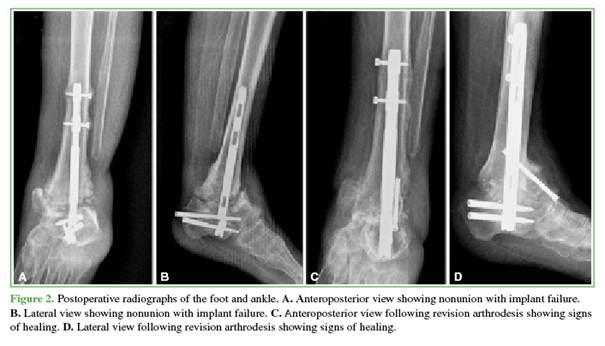

Three patients required revision arthrodesis: one due to implant failure following a fall and two due to nonunion (Figures 1 and 2). Revision procedures involved implant removal, debridement of the arthrodesis site, and re-arthrodesis using a new nail. All revision surgeries were preceded by optimization of metabolic parameters and comorbidities.

At the end of follow-up, seven patients had achieved stable healing of the TTC arthrodesis (Figures 3 and 4). Two developed fibrous healing, which allowed ambulation with orthotic support. One patient required a delayed revision and remains under follow-up. The median time to radiographic healing was 8.6 months (IQR 25-75%: 4.7–8.6).